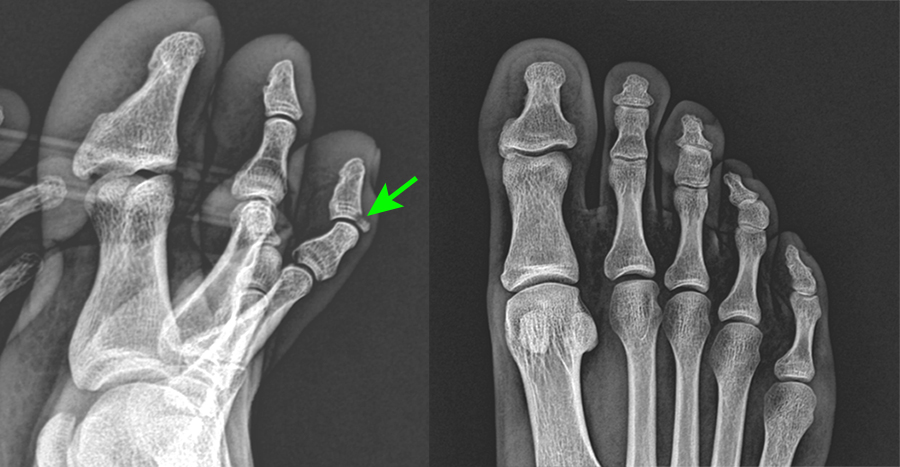

오른쪽 엑스레이에는 정상처럼 별 표시가 안나는데, 왼쪽측면에서 찍었을대는 의사 말씀이 화살표 부분이 골절되었다고 한다. 일반인인 내가 봐도 딱 티가 난다.

발가락 관절부분 인대와 그 아래 뼈와 같이 약간 떨어져 나가 골절이 되었다고 한다. 일단 골절이 되었으니 이상태로 굳어 버리면 위로 잘 젖혀지지 않는다고 한다. 그래서 뒤에 큰 종합병원이 있으니 진료의뢰서를 작성해 줄 테니 가서 핀을 박아 수술을 하라는 것이었다. 단, 수술을 안 해도 크게 문제가 없다는 말도 덧붙였다.